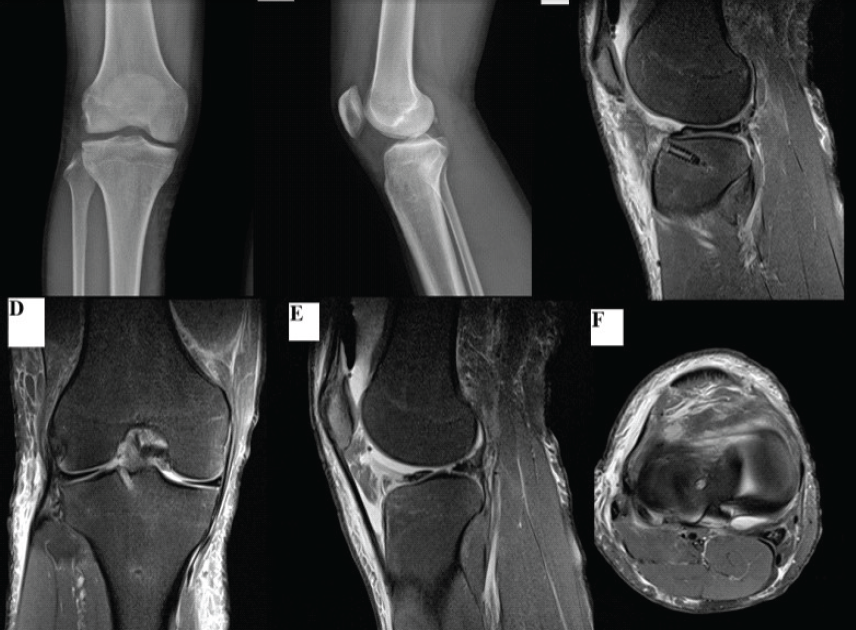

Postoperatively, the knee was immobilized in extension for 1 week, followed by a progressive range of motion up to 90° for 4 weeks. Partial weight bearing began at 6 weeks and full weight bearing at 8–10 weeks. At 6 months, the patient demonstrated a full range of motion without pain or effusion. The Lysholm score was 95, IKDC 92, and KOOS-Pain 90. Follow-up MRI showed an intact, healed meniscus with no residual tear or extrusion (Fig. 4). The patient resumed light football training after 5 months.

Figure 4: Post-operative imaging of the right knee following circumferential fiber augmentation (CFA) repair of a bucket-handle tear in the discoid lateral meniscus. (a) Anteroposterior knee radiograph showing restoration of joint space and correction of flexion deformity. (b) Lateral knee radiograph demonstrating maintained reduction of the meniscus. (c) Sagittal T2-weighted magnetic resonance imaging (MRI) showing anatomical reduction of the meniscus with resolution of the “double posterior cruciate ligament” sign. (d) Coronal T2-weighted MRI confirming a stable meniscal contour without a displaced fragment. (e) Sagittal T2-weighted MRI showing continuity of the repaired discoid meniscus with preserved thickness. (f) Axial MRI demonstrating a well-seated meniscus without a displaced fragment or double-layer appearance.